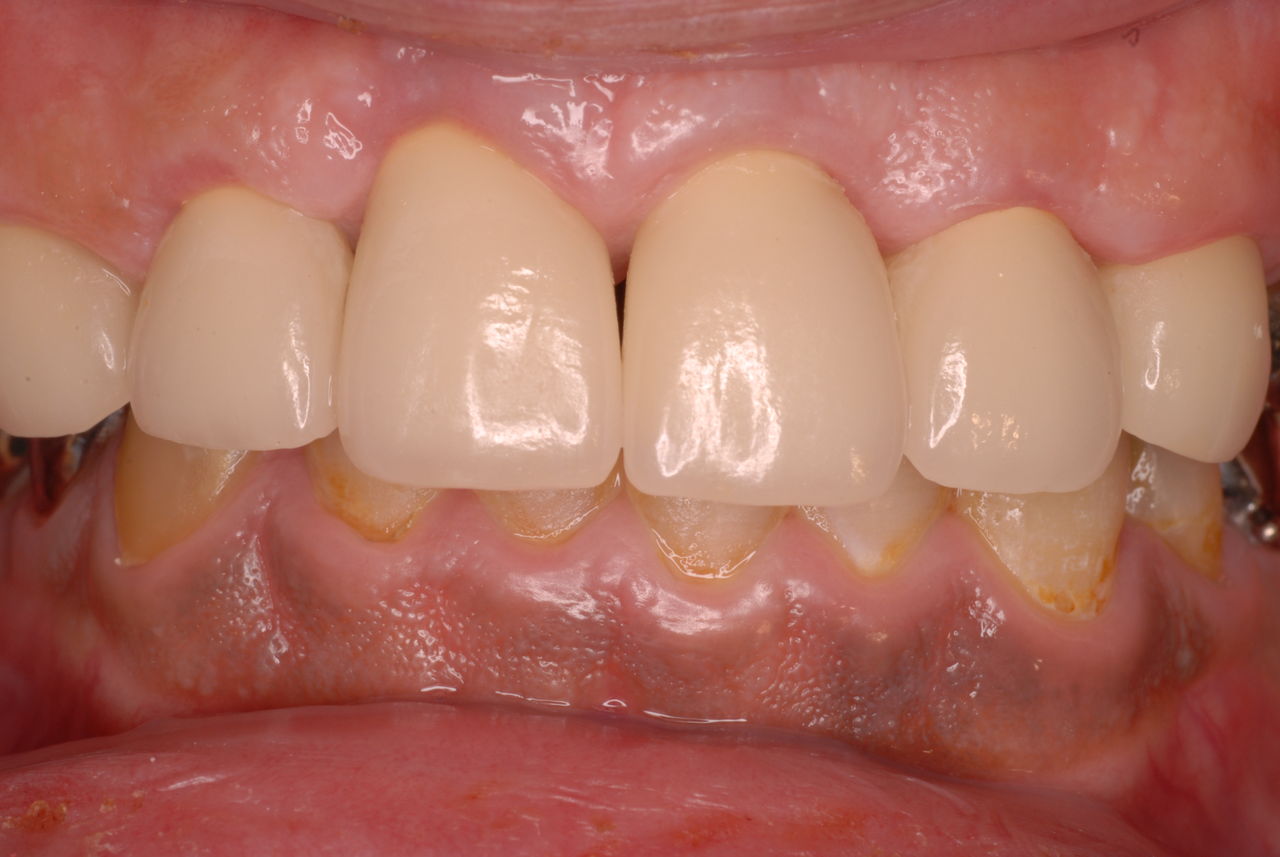

30代の男性の方です。

入れ歯を入れていました。歯科医院で歯を抜けず仕方なく入れ歯にしたとか。何とかならないものだったのか悔やまれました。

抜いた歯はありません。

一応差し歯にしましたが、歯茎の状態はよくはありません。

とりあえず希望を入れて差し歯にしたような感じです。